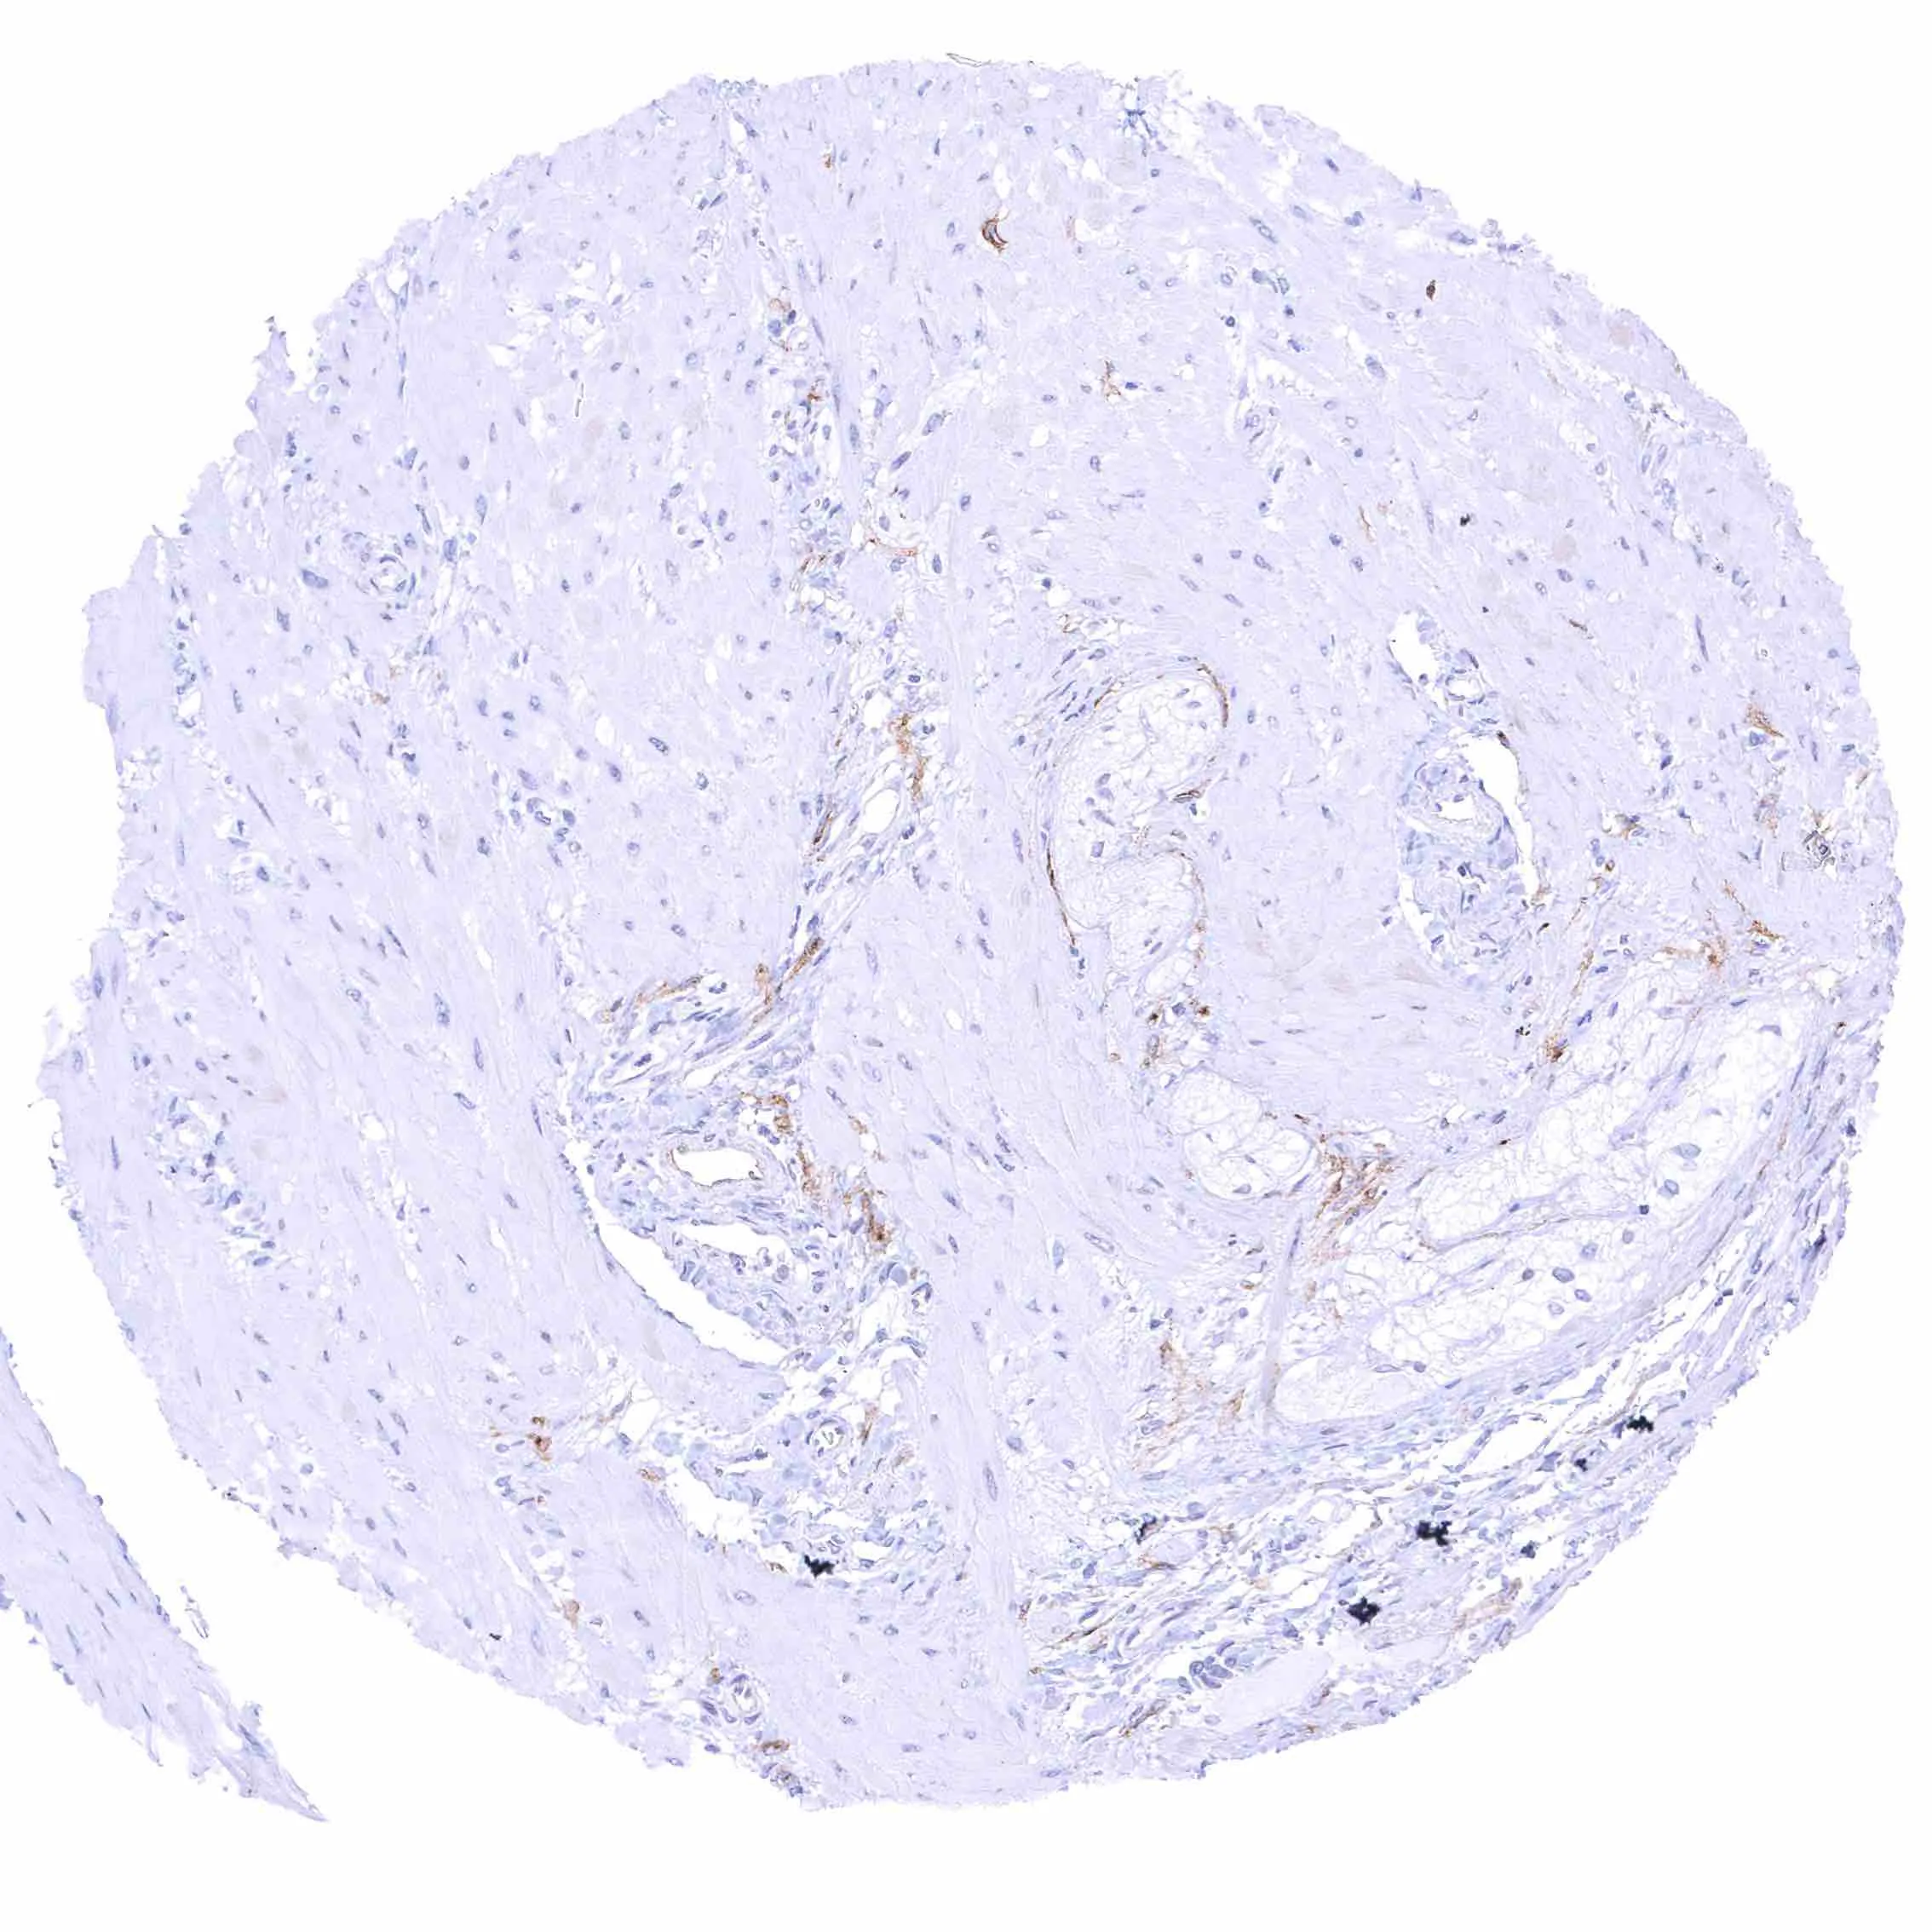

Uterus, myometrium – Distinct NPR-C staining of endothelial cells in some but not all blood vessels